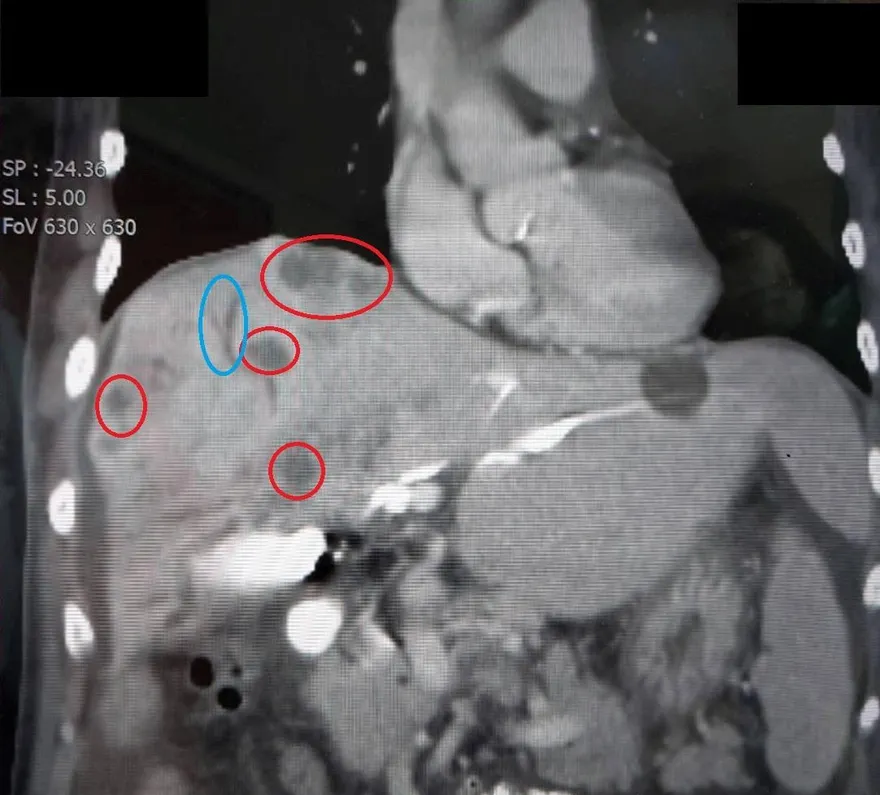

淋巴瘤

淋巴結腫大

何杰金氏淋巴瘤

非何杰金氏淋巴瘤

惡性淋巴瘤

淋巴腺腫大

惡性腫瘤

瀰漫性大B細胞淋巴癌